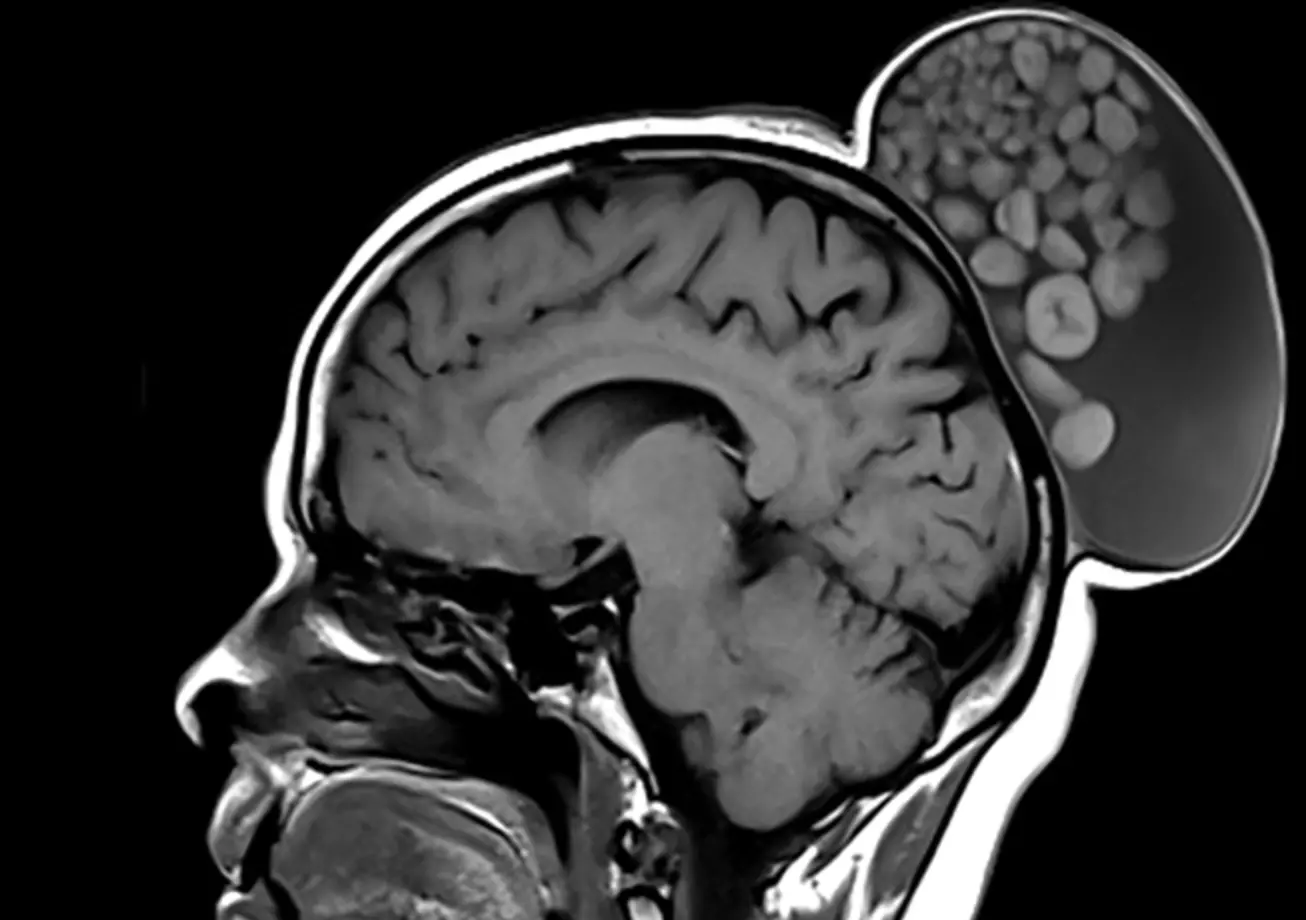

Un kyste ressemblant à "un sac de billes". C’est l’étonnant cas clinique qu’a partagé une équipe de chercheurs indiens de l'Institut des sciences médicales supérieures Sri Sathya Sai dans la revue médicale Radiology, indique le New York Post.

Lorsqu’elle a enfin cherché à obtenir une aide médicale, le kyste avait grossi jusqu’à mesurer plus de 15 cm de long et 10 cm de large. L’équipe médicale a donc décidé d’opérer leur patiente. Lors de son ablation, ils ont remarqué que le kyste était rempli de liquide, de cheveux, de molécules grasses et d’amas de kératine “de tailles variées”.